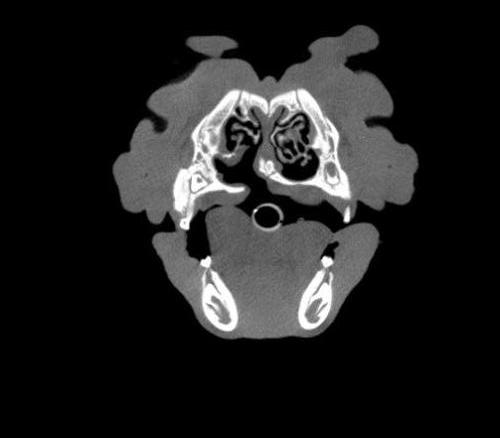

The Center now provides advanced imaging via cone beam CT. Cone beam CT is excellent for visualization of bony structures of the skull, nasal cavity, teeth, and ears. Cone beam CT is especially helpful for diagnosing dental disease and evaluation of jaw fractures. It can also be useful for evaluating the sinuses and tympanic bulla. Cone beam CT can be used in conjunction with nasal biopsy and culture to evaluate nasal discharge whether chronic or acute.

Pets can be involved in trauma that can cause fractures to their head, teeth, and jaw bones. Correctly repairing these fractures is extremely important for your pet to have normal function of their mouth. If a jaw fracture is allowed to heal in an abnormal position, your pet may have great difficulty chewing and can be in significant pain. Many fractures can be successfully treated with minimally invasive oral procedures, but more complicated cases may require bone plating techniques. The Center offers cone beam CT imaging which provides extremely detailed images of the bones of the head and skull. Advanced imaging with CBCT facilitates selection of the best surgical technique to get your pet back to eating and comfort as soon as possible.